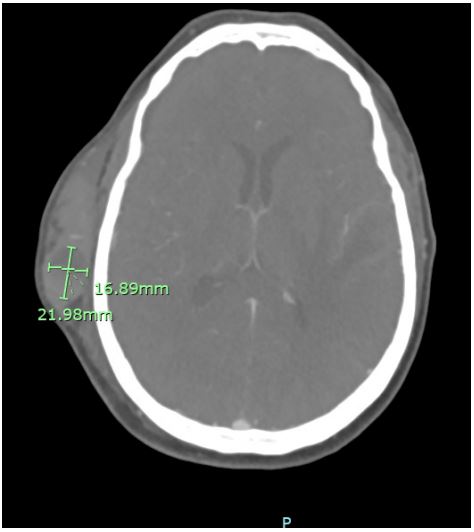

Upon arrival, CT of the head showed a large right frontotemporal scalp hematoma with hematocrit levels suggesting recent/active hemorrhage, no acute intracranial hemorrhage or extra axial collection, and left temporal encephalomalacia and gliosis likely related to prior treatment/ischemic insult with superimposed acute ischemia. CTA of the head/neck showed patent intracranial arteries without significant stenosis, occlusion, or aneurysm, a small amount of internal cerebral venous drainage, and a large superficial scalp hematoma over the right frontotemporal bone with active extravasation from the right superficial temporal artery. Both right and left internal carotid arteries showed no hemodynamically significant stenosis by NASCET criteria.

Figure 2: CT Head Angiogram. Large superficial scalp hematoma over the right frontotemporal bone with active extravasation from the right superficial temporal artery 2.3 cm x 1.7 cm.

Figure 3: CT Head Non-contrast. Large right frontotemporal scalp hematoma.